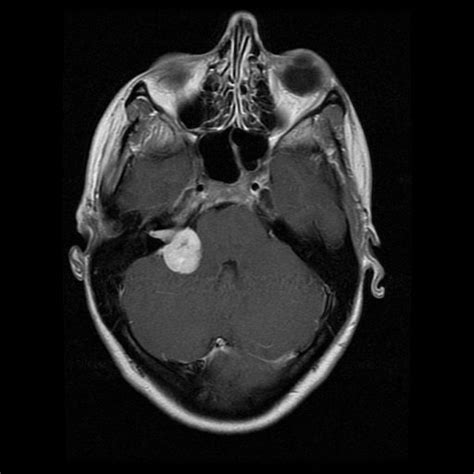

MRT-Scan eines Akustikusneurinoms

- Kernspin 11/2010: Nur geringe postoperative-narbige Restveränderungen ohne Anhalt für neuerliches Tumorwachstum bzw. Lokalrezidiv.

Zudem erwähnte er eine kleine Kontrastmittelanreicherung, die ein Blutgefäß, Narbengewebe, aber auch ein neuer Tumor oder Tumorrest sein könnte. Deswegen alleine würde man aber nicht operieren, sondern ggf. bestrahlen. Eine OP wegen Schwindel hätte den Vorteil, dass man da nochmal draufschauen könne.

Sein schriftlicher Befund wies jedoch aus: ... linksseitig keine Hinweise für ein Lokalrezidiv, lediglich ist aktuell Narbengewebe ersichtlich.